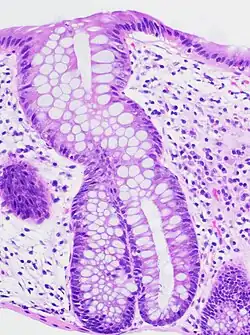

A micrograph demonstrating cryptitis, a microscopic correlate of colitis. H&E stain.

An important investigation in the assessment of colitis is biopsy for histopathology. A very small piece of tissue (usually about 2mm) is removed from the bowel mucosa during endoscopy and examined under the microscope by a histopathologist. A biopsy report generally does not state the diagnosis, but should state any presence of chronic colitis, give an indication of disease activity, as well as state the presence of any epithelial damage (erosions and ulcerations).[6]